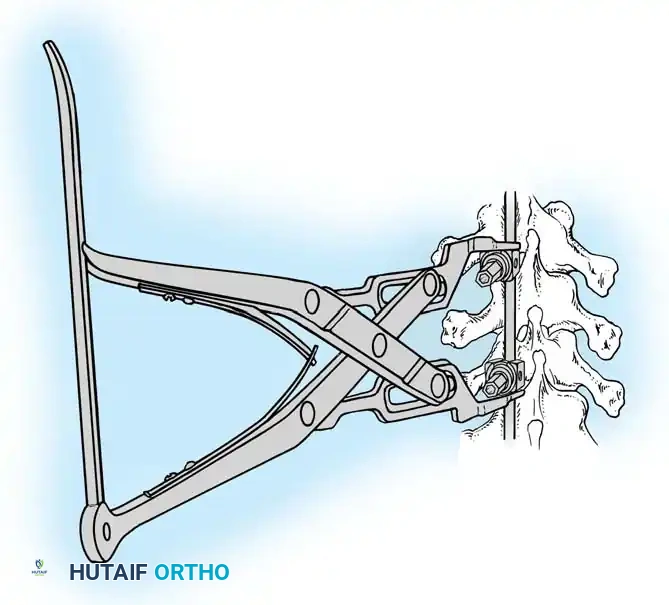

PREOPERATIVE PLANNING AND PATIENT POSITIONING

Meticulous patient positioning is the first and arguably one of the most critical steps in posterior spinal surgery. Proper positioning mitigates intraoperative complications, reduces blood loss, and fundamentally dictates the final sagittal profile of the instrumented spine.

Fig. 38-22: Patient positioning on a Jackson table with hips in extension to maintain physiological lumbar lordosis.

Positioning on the Jackson Table

- Prone Positioning: The patient is carefully rolled prone onto an open-frame Jackson table (e.g., Mizuho OSI, Union City, Calif). The open frame is paramount as it allows the abdomen to hang free.

- Hemodynamic Optimization: Eliminating intra-abdominal pressure prevents compression of the inferior vena cava. This directly reduces venous engorgement within Batson’s epidural venous plexus, drastically minimizing intraoperative blood loss during exposure and pedicle cannulation.

- Neurological Protection: The arms must be meticulously supported on arm boards with all bony prominences (especially the elbows and ulnar nerves) heavily padded.

- Brachial Plexus Precaution: Do not abduct the shoulders beyond 90 degrees. Excessive abduction or extension places undue traction on the brachial plexus, risking postoperative neuropraxia.

- Chest Pad Placement: Ensure the upper pads of the frame rest squarely on the bony thorax (rib cage/sternum) and do not migrate into the axilla, which could compress the neurovascular bundle.

Surgical Warning: When a patient is positioned prone with the hips flexed, physiological lumbar lordosis is artificially obliterated. If the planned fusion extends into the lower lumbar spine (L3, L4, or L5), it is imperative to elevate the knees and thighs so the hip joints are fully extended. This maneuver restores and locks in normal lumbar lordosis, which is critical for preventing postoperative flatback syndrome and adjacent segment disease.